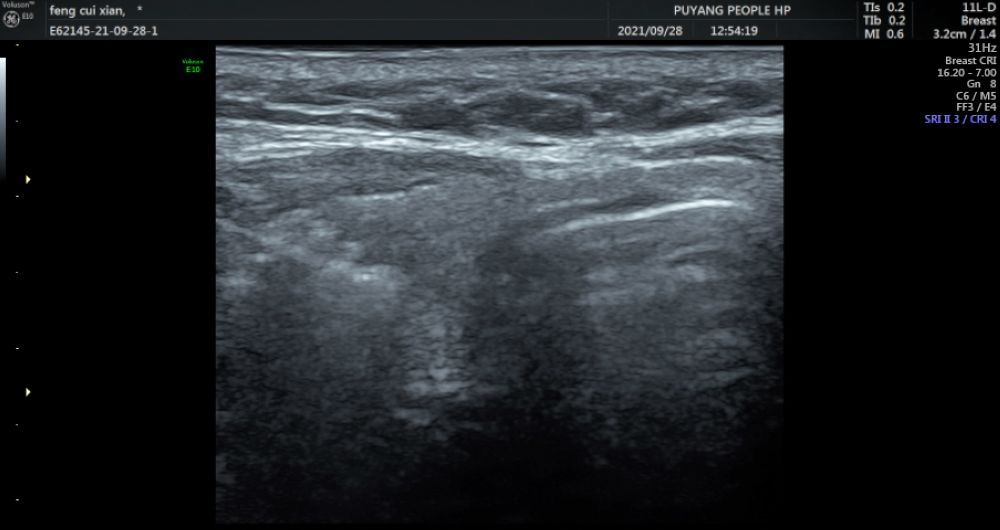

圖2

患者馮某某,女,21歲,大三在讀,在濮陽(yáng)市人民醫(yī)院超聲科進(jìn)行頸部超聲檢查后,發(fā)現(xiàn)右側(cè)葉甲狀腺類結(jié)節(jié)(圖1),并且經(jīng)過活檢穿刺病理為不能除外甲狀腺乳頭狀癌(圖2),這如同一個(gè)晴天霹靂般的壞消息,讓患者難以接受,如花綻放般的年齡,卻要面對(duì)如此殘酷的抉擇。如果選擇手術(shù)切除,術(shù)后頸部的瘢痕、終身服藥的不便成為了現(xiàn)實(shí)難題,讓馮某某難以接受傳統(tǒng)手術(shù)療法。在了解到她的困擾后,濮陽(yáng)市人民醫(yī)院甲狀腺乳腺外科迅速啟動(dòng)科內(nèi)會(huì)診及病例討論機(jī)制,在學(xué)科主任王仁啟主任的提議下,決定采用超聲引導(dǎo)下的射頻消融治療,對(duì)馮某某的惡性結(jié)節(jié)進(jìn)行局部滅活,并且盡可能保留正常腺體。通過術(shù)前評(píng)估,細(xì)致準(zhǔn)備,消融手術(shù)由超聲科主任李亞敏副主任親自主刀。在實(shí)時(shí)超聲的引導(dǎo)下,射頻消融針精準(zhǔn)的進(jìn)入惡性病灶內(nèi),僅用時(shí)3分鐘左右,消融范圍就完全覆蓋病灶并局部擴(kuò)大消融范圍(圖3)。